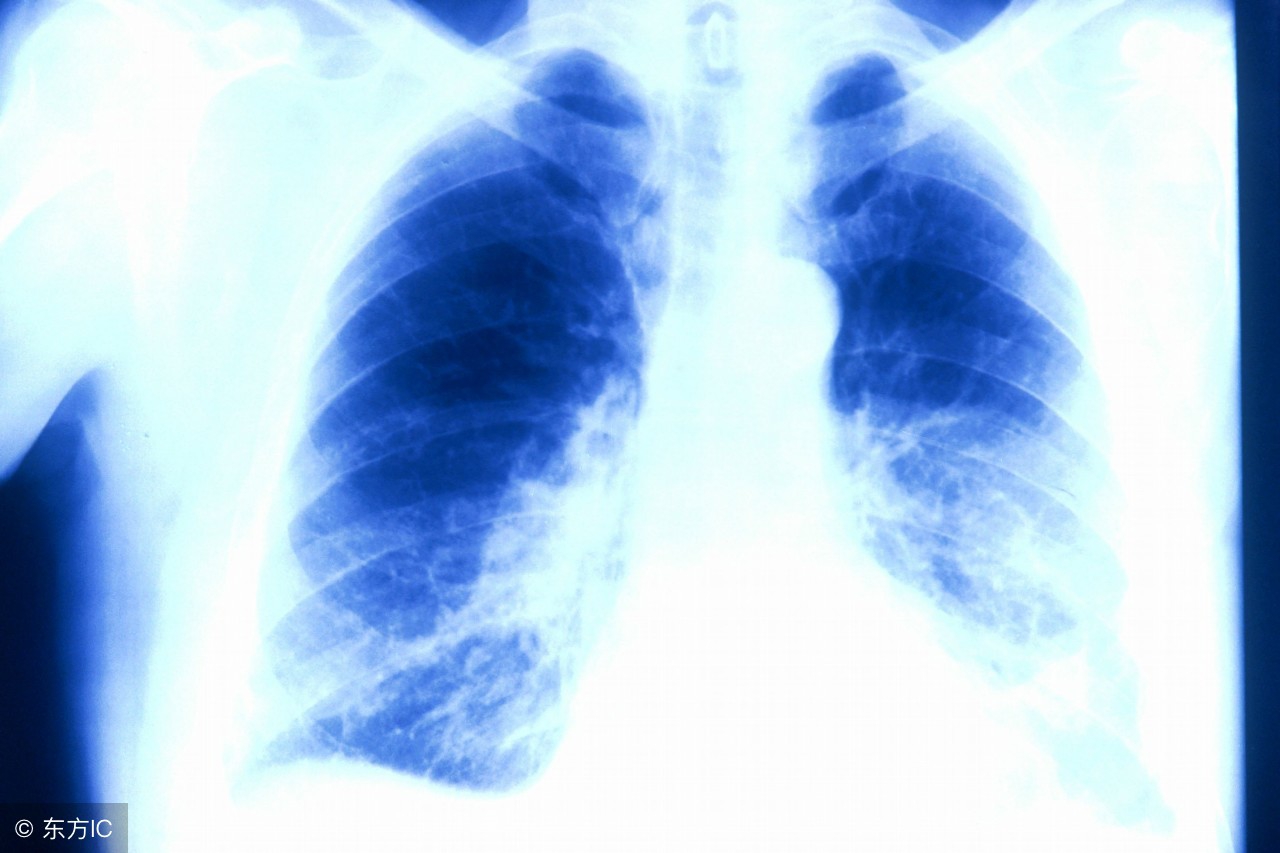

注:文中图片来自网络,如有侵权请联系删除